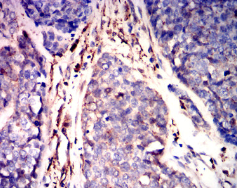

GSN Mouse Monoclonal antibody[5E3B9]

Species Reactivity:    Human

IHC    1/200-1/1000